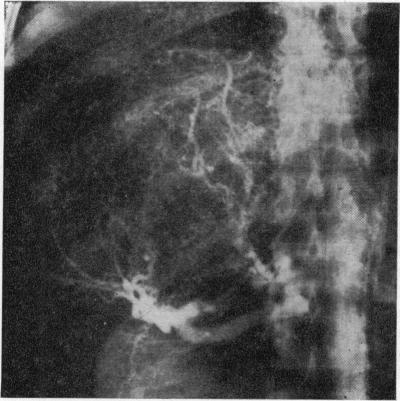

Angiography in the diagnosis of liver tumours.

Proc R Soc Med. 1974 Mar;67(3):208-11. doi: 10.1177/003591577406700317.